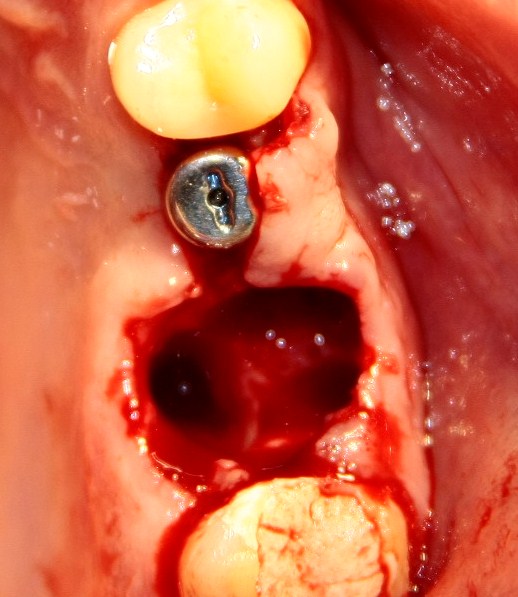

Немедленная имплантация — оптимальное решение в любой клинической ситуации